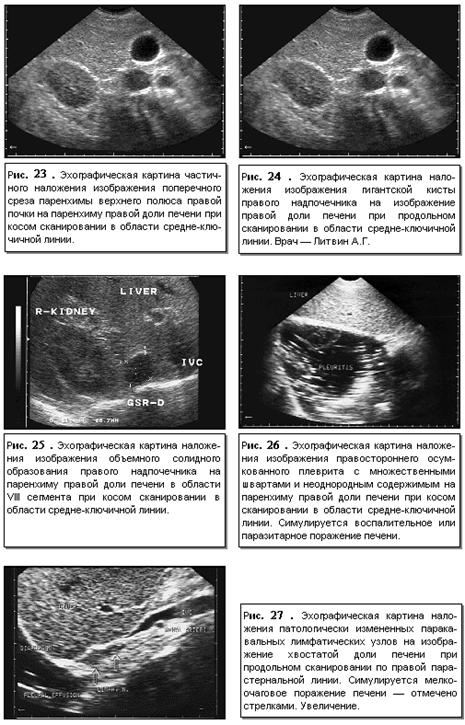

Определенное

влияние на качество и характер изображения печени может оказывать наложение

изображения прилегающих органов и структур и патологических процессов в них

(рис. 23-27).